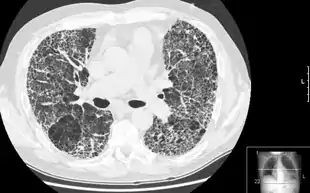

مرض رئوي خلالي

مرض رئوي خلالي (بالإنجليزية: Interstitial lung disease)، يشير إلى مجموعة من الأمراض الرئوية التي تصيب النسيج الخلالي الرئوي (النسيج والفراغ حول الحويصلات الهوائية الرئوية).[2] المرض الرئوي الخلالي قد يؤدي إذا كان مزمناً إلى تليف رئوي.

![]() مرض رئوي خلالي - يثمثل في رئة شبيهة بعش النحل مرض رئوي خلالي - يثمثل في رئة شبيهة بعش النحل | |

الفحوصات تتضمن تحاليل دم وصورة أشعة للصدر وفحص وظائف الرئة وصورة طبقية عالية الجودة لمنطقة الظهر. قد يتم أخذ خزعة من الرئة إذا لم يستطع الطبيب معرفة السبب عبر السيرة المرضية أو لا يمكن إستثناء أية سرطانات.